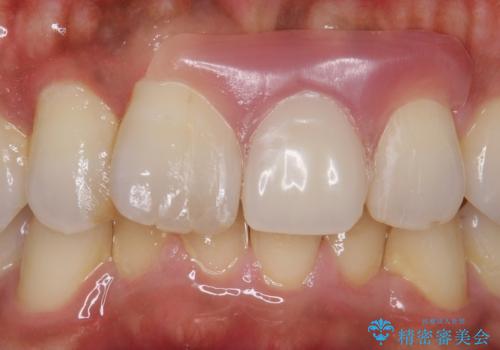

- 抜歯になった前歯を入れ歯で治療した症例です。

前歯部なので金属の留め金を使わない、審美性に優れたノンクラスプデンチャーによる補綴を行いました。

ノンクラスプデンチャーは従来の入れ歯と異なり金属の留め金を使用しないため、非常に審美性に優れた入れ歯です。